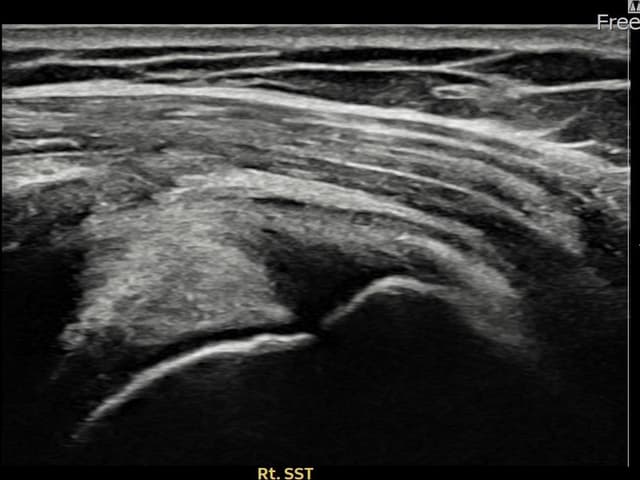

実際の患者様の施術前後の超音波画像。

手術なしで実現できる回復をご確認ください。

[経過期間: 23.09.19~23.11.21]

[縫縮術] 超音波検査にて右 棘上筋腱 関節面側部分断裂(9mm × 4mm (腱厚の約38%欠損))を確認。縫縮術施行後、腱の連続性が回復し、日常生活に復帰されました。